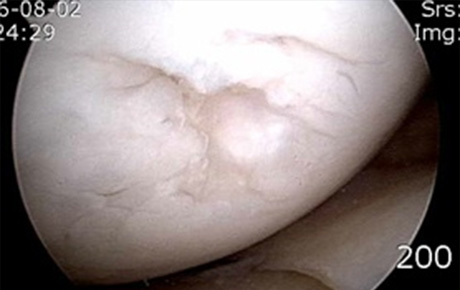

연골세포는 종의 배열로 작은 세포들이 배열되어 있는

조직입니다. 특히, 혈관조직이 이런 연골세포 쪽으로는

없기 때문에 연골이 손상된다면 재생이 되기가 어렵습니다.

- 환자 동의하에

게시된 이미지입니다.